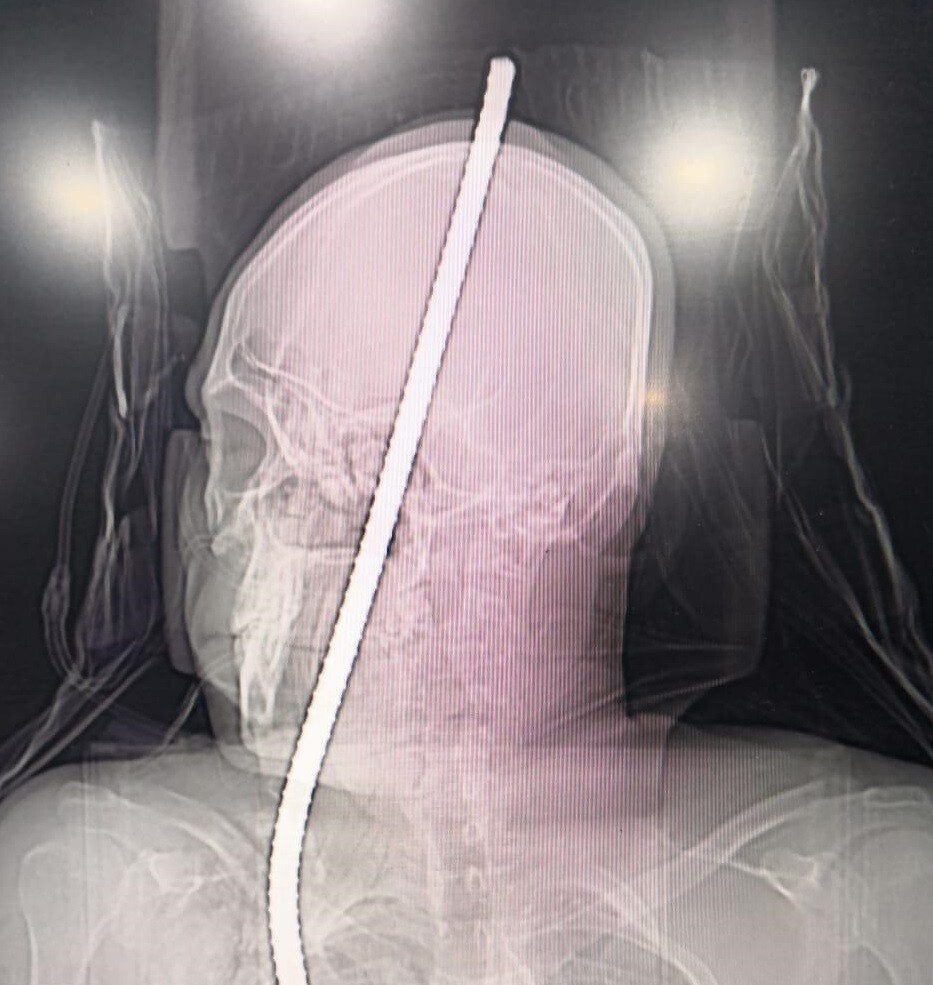

यूँ ही डॉक्टरों को भगवान नहीं कहा जाता, मजदूरी कर अपने परिवार का पेट पालने वाले राकेश जाधव के साथ जो हुआ उसे केवल भगवान का ही सहारा था। दरअसल राकेश एक निर्माणाधीन बिल्डिंग में काम करते 13 फूट की ऊंचाई से नीचे गिर पड़ा,और उसके सीने में एक लोहे का रॉड घुस गया जो सिर से होते हुए बाहर निकल आया था। आख़िरकार डॉक्टरों ने राकेश को बचा लिया, लेकिन कैसे पढ़िए इस रिपोर्ट में।

मंगलवार 20 नवंबर के दिन चेंबूर की एक निर्माणाधीन बिल्डिंग में राकेश जाधव काम कर रहा था। काम करते समय राकेश का संतुलन अचानक बिगड़ गया और वह 13 फूट नीचे आ गिरा। इस हादसे में राकेश के सीने में एक 3 फूट लोहे का रॉड घुस गया जिसका एक सिरा सिर के रास्ते बाहर निकल आया। राकेश का काफी खून बह चुका था, उसे तत्काल जेन अस्पताल में दाखिल कराया गया।

अस्पताल के डॉक्टरों ने भी इस एक चुनौती के रूप में लेते हुए राकेश का इलाज करना शुरू किया। न्यूरोसर्जन डॉ बटुक डिओरा, डॉ. प्रमोद मस्जीद, डॉ. प्रमोद काले सहित अन्य डॉक्टरों ने मिल कर राकेश का इलाज करना शुरू किया। आखिर 5 घंटे कठिन ऑपरेशन करने के बाद डॉक्टरों ने राकेश के शरीर से सफ़लतपूर्वक लोहे की रॉड बाहर निकालने में सफलता पाई। डॉक्टरों के मुताबिक अब राकेश की स्थिति स्थिर है लेकिन जख्म को भरने में समय लगेगा।